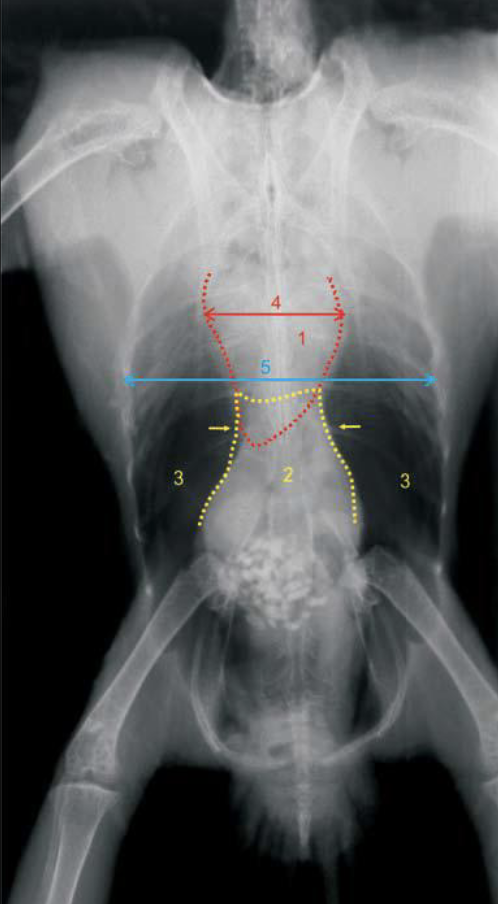

What are the anatomical structures labelled in this image?

A

1: heart silhouette

2: liver silhouette

4: cardiac width

5: thoracic width

How should cardiac width compare to thoracic width in medium sized parrots?

cardiac width should be 50-60% of thoracic width